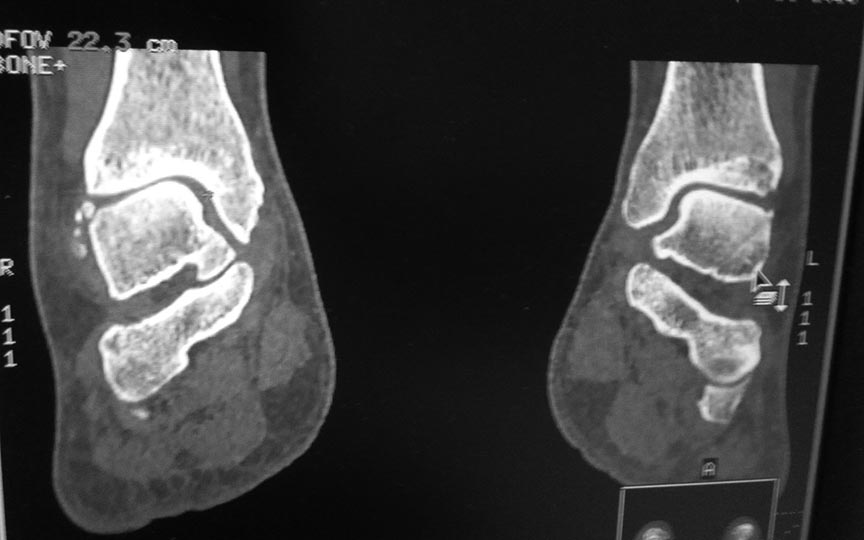

Добрый день!Обратилась женщина 1975 г.р. Жалобы на боль в голеностопном суставе при нагрузке (после ходьбы на расстояние 200 метров).

Травма три года назад. Упала с высоты своего роста, подвернула ногу, лечилась амбулаторно с Ds : растяжение связок голеностопного сустава. Rg не делали. После травмы боль осталась, в динамике интенсивность боли прогрессировала. Ухудшение в течении последних 6 мес. Местно : движения в голеностопном суставе в полном обьеме, отек незначительный. Пальпация безболезненна.Rg, Кт прилагается.Какова на ваш взгляд тактика лечения в данном случае?

Неплохо подвернула ногу))) А то что стопа смотрит во внутрь ее не беспокоит? Тактика - однозначно оперировать и быть готовым к 2 вариантам лечения: если суставной хрящ не поврежден - то восстанавливать анатомическое взаимоотношений в суставе, как на мягкотканном уровне, так и в плане корригирующих остеотомий. Если же хрящ побитый, то артродез голеностопного сустава.

Интересный случай. А рентген сделан под нагрузкой? Не похоже. Обязательно нужно под нагрузкой сделать. И обещанной КТ что-то не видно. Артроз тут, конечно, есть. Хотя далеко не крайняя степень. Думать об артродезе вроде рановато. Но и какого рада корригирующая остеотомия могла бы помочь тоже по этим снимкам не скажешь.

Изменения не только в голеностопном суставе, но и, мне так кажется, в прилегающих суставах. Процесс не достаточно старый. Может исход приспособительной перестройки на фоне паралитического процесса.